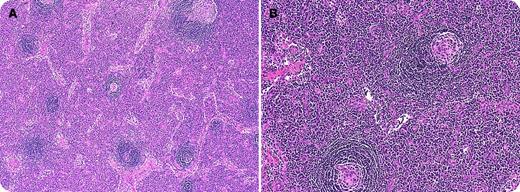

A 48-year-old woman presented with a 2-week history of peripheral neuropathy. She progressively developed motor weakness leading to quadriparesis and respiratory failure requiring intubation. Nerve conduction studies showed diffuse absence of motor and sensory responses. She had a right cervical mass that was excised, which showed regressed follicles with expansion of interfollicular region by sheets of plasma cells. The majority of the follicles contained lymphocyte-depleted germinal center surrounded by a broad mantle zone with an “onion skin” pattern (panel A); some follicles were penetrated by hyalinized blood vessels (panel B). The bone marrow biopsy showed thickened trabeculae and increased atypical megakaryocytes. The overall features were suggestive of Castleman disease, plasma cell variant. Serum immunofixation showed monoclonal IgG λ (M-spike, 0.8 g/dL); vascular endothelial growth factor level was elevated at 1101 pg/mL. A diagnosis of POEMS (polyneuropathy, organomegaly, endocrinopathy, monoclonal gammopathy and skin changes) syndrome was made. She was treated with cyclophosphamide and dexamethasone. With four cycles of treatment, she regained upper extremity strength and is now ventilator independent.

POEMS syndrome is a rare paraneoplastic syndrome resulting from an underlying plasma cell disorder. The diagnosis is often delayed because of incorrect diagnoses of chronic inflammatory demyelinating polyradiculoneuropathy and monoclonal gammopathy of undetermined significance. Between 11% and 30% of patients with POEMS have documented Castleman disease or Castleman-like histology. Prompt treatment directed at the plasma cell clone produces good responses in majority of the patients.